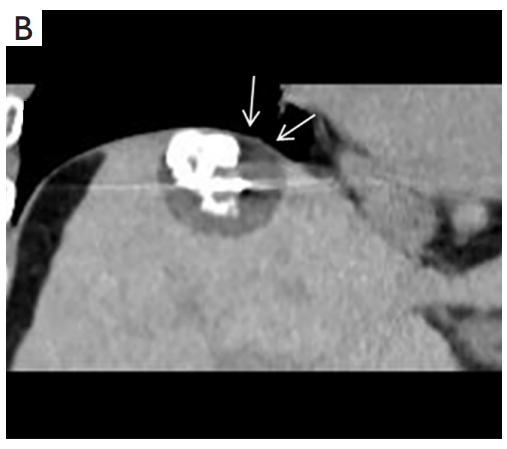

背景:肝癌是中國最常見的惡性腫瘤之一,發(fā)病率和死亡率都很高。雖然手術(shù)切除是最好的治療方法,但大多數(shù)患者處于晚期或直到住院才有手術(shù)指征。對于單個腫瘤直徑小于5厘米的患者,微創(chuàng)治療與手術(shù)切除效果相當;多個病灶小于3個,單個病灶最大直徑小于3cm;不侵犯血管、膽管、鄰近器官和遠處轉(zhuǎn)移。雖然一些傳統(tǒng)消融技術(shù)方式可以使部分患者受益,但不適用于特殊部位肝癌(定義為毗鄰大血管、肝外臟器和重要結(jié)構(gòu)的腫瘤)的治療。冷凍消融作為一種相對較新的治療方式,具有明顯的冰球效果、療效好、激活抗腫瘤免疫、并發(fā)癥發(fā)生率低等優(yōu)點,尤其適用于特殊部位肝癌患者的治療。我們的研究目的是探討CA治療特殊部位肝癌的安全性、可行性和有效性。

① 在我們的研究中,技術(shù)成功率為100%。動態(tài)增強MR檢查隨訪1個月,66例患者首次技術(shù)有效率為65例(98.5%),MR影像學未發(fā)現(xiàn)外周臟器損傷。中位隨訪時間14個月(范圍2-28個月)。高危部位肝癌局部腫瘤進展率曲線:6、9、15和24個月的累積局部腫瘤進展率分別為10.2%、16.5%、20.9%和30.5%。